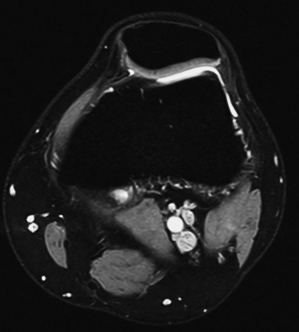

La Resonancia magnética (RMN) es un método de imagen multiplanar no invasivo, basado en la interacción entre la radiofrecuencia, los campos magnéticos y ciertos núcleos en el cuerpo humano (generalmente núcleos de hidrógeno del agua), después que el cuerpo ha sido introducido en un campo magnético fuerte. La información obtenida es procesada por un ordenador y transformada en imágenes del cuerpo humano.

La RM consigue información sobre la estructura del cuerpo permitiendo diferenciar entre tejidos normales y anormales lo que la convierte en una técnica muy sensible para detectar enfermedad. Esta sensibilidad está basada en un alto grado de contraste debido a las variaciones en las propiedades de relajación magnética de los diferentes tejidos, tanto normales como anormales.